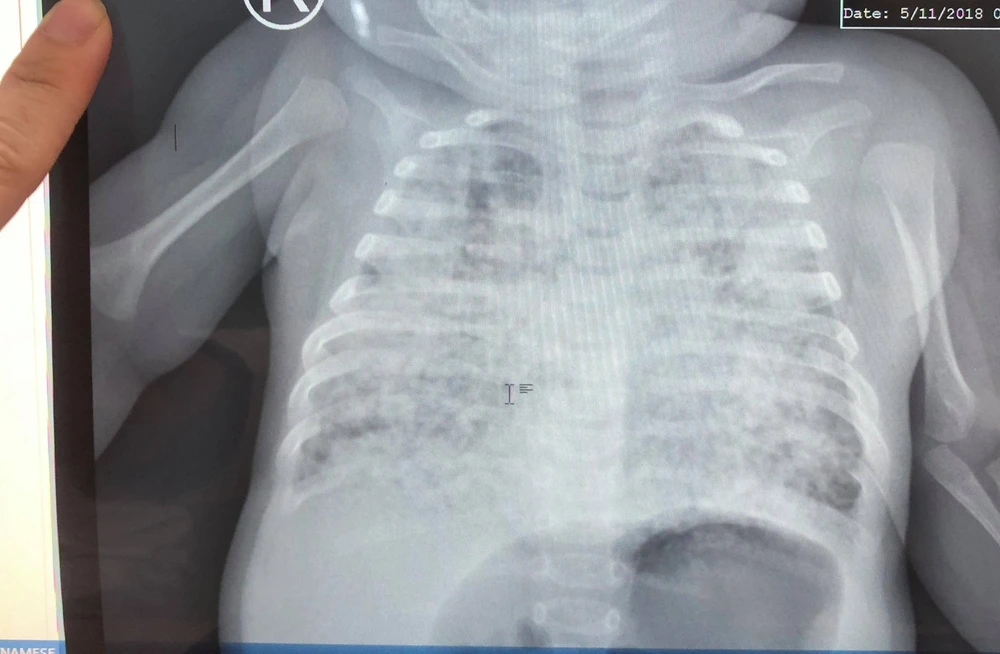

BS Vũ kể lại khoảng 3 tháng trước, bé N. được người nhà đưa từ An Giang đến BV cấp cứu trong tình trạng nhiễm lao kê nặng, chụp phim phổi trắng xóa.

Phim phổi tổn thương trắng xóa, lấm tấm do lao kê của bé khi mới nhập viện điều trị. Ảnh: BSCC

Trong quá trình điều trị, kén khí do các ổ lao vỡ liên tục gây tràn khí màng phổi cho bé 4 lần. Bé phải thở máy kéo dài, suy hô hấp nặng đến thở máy rung tần số cao, lệ thuộc oxy hơn 3 tháng tưởng chừng không còn cơ hội sống…

Nhờ được theo dõi điều trị tích cực hơn 3,5 tháng tại BV, phổi bé sáng dần lên, mô phổi giảm tổn thương và thông khí ngày càng hiệu quả, các kén khí lớn giảm rõ rệt nên bé đã cai được máy thở.